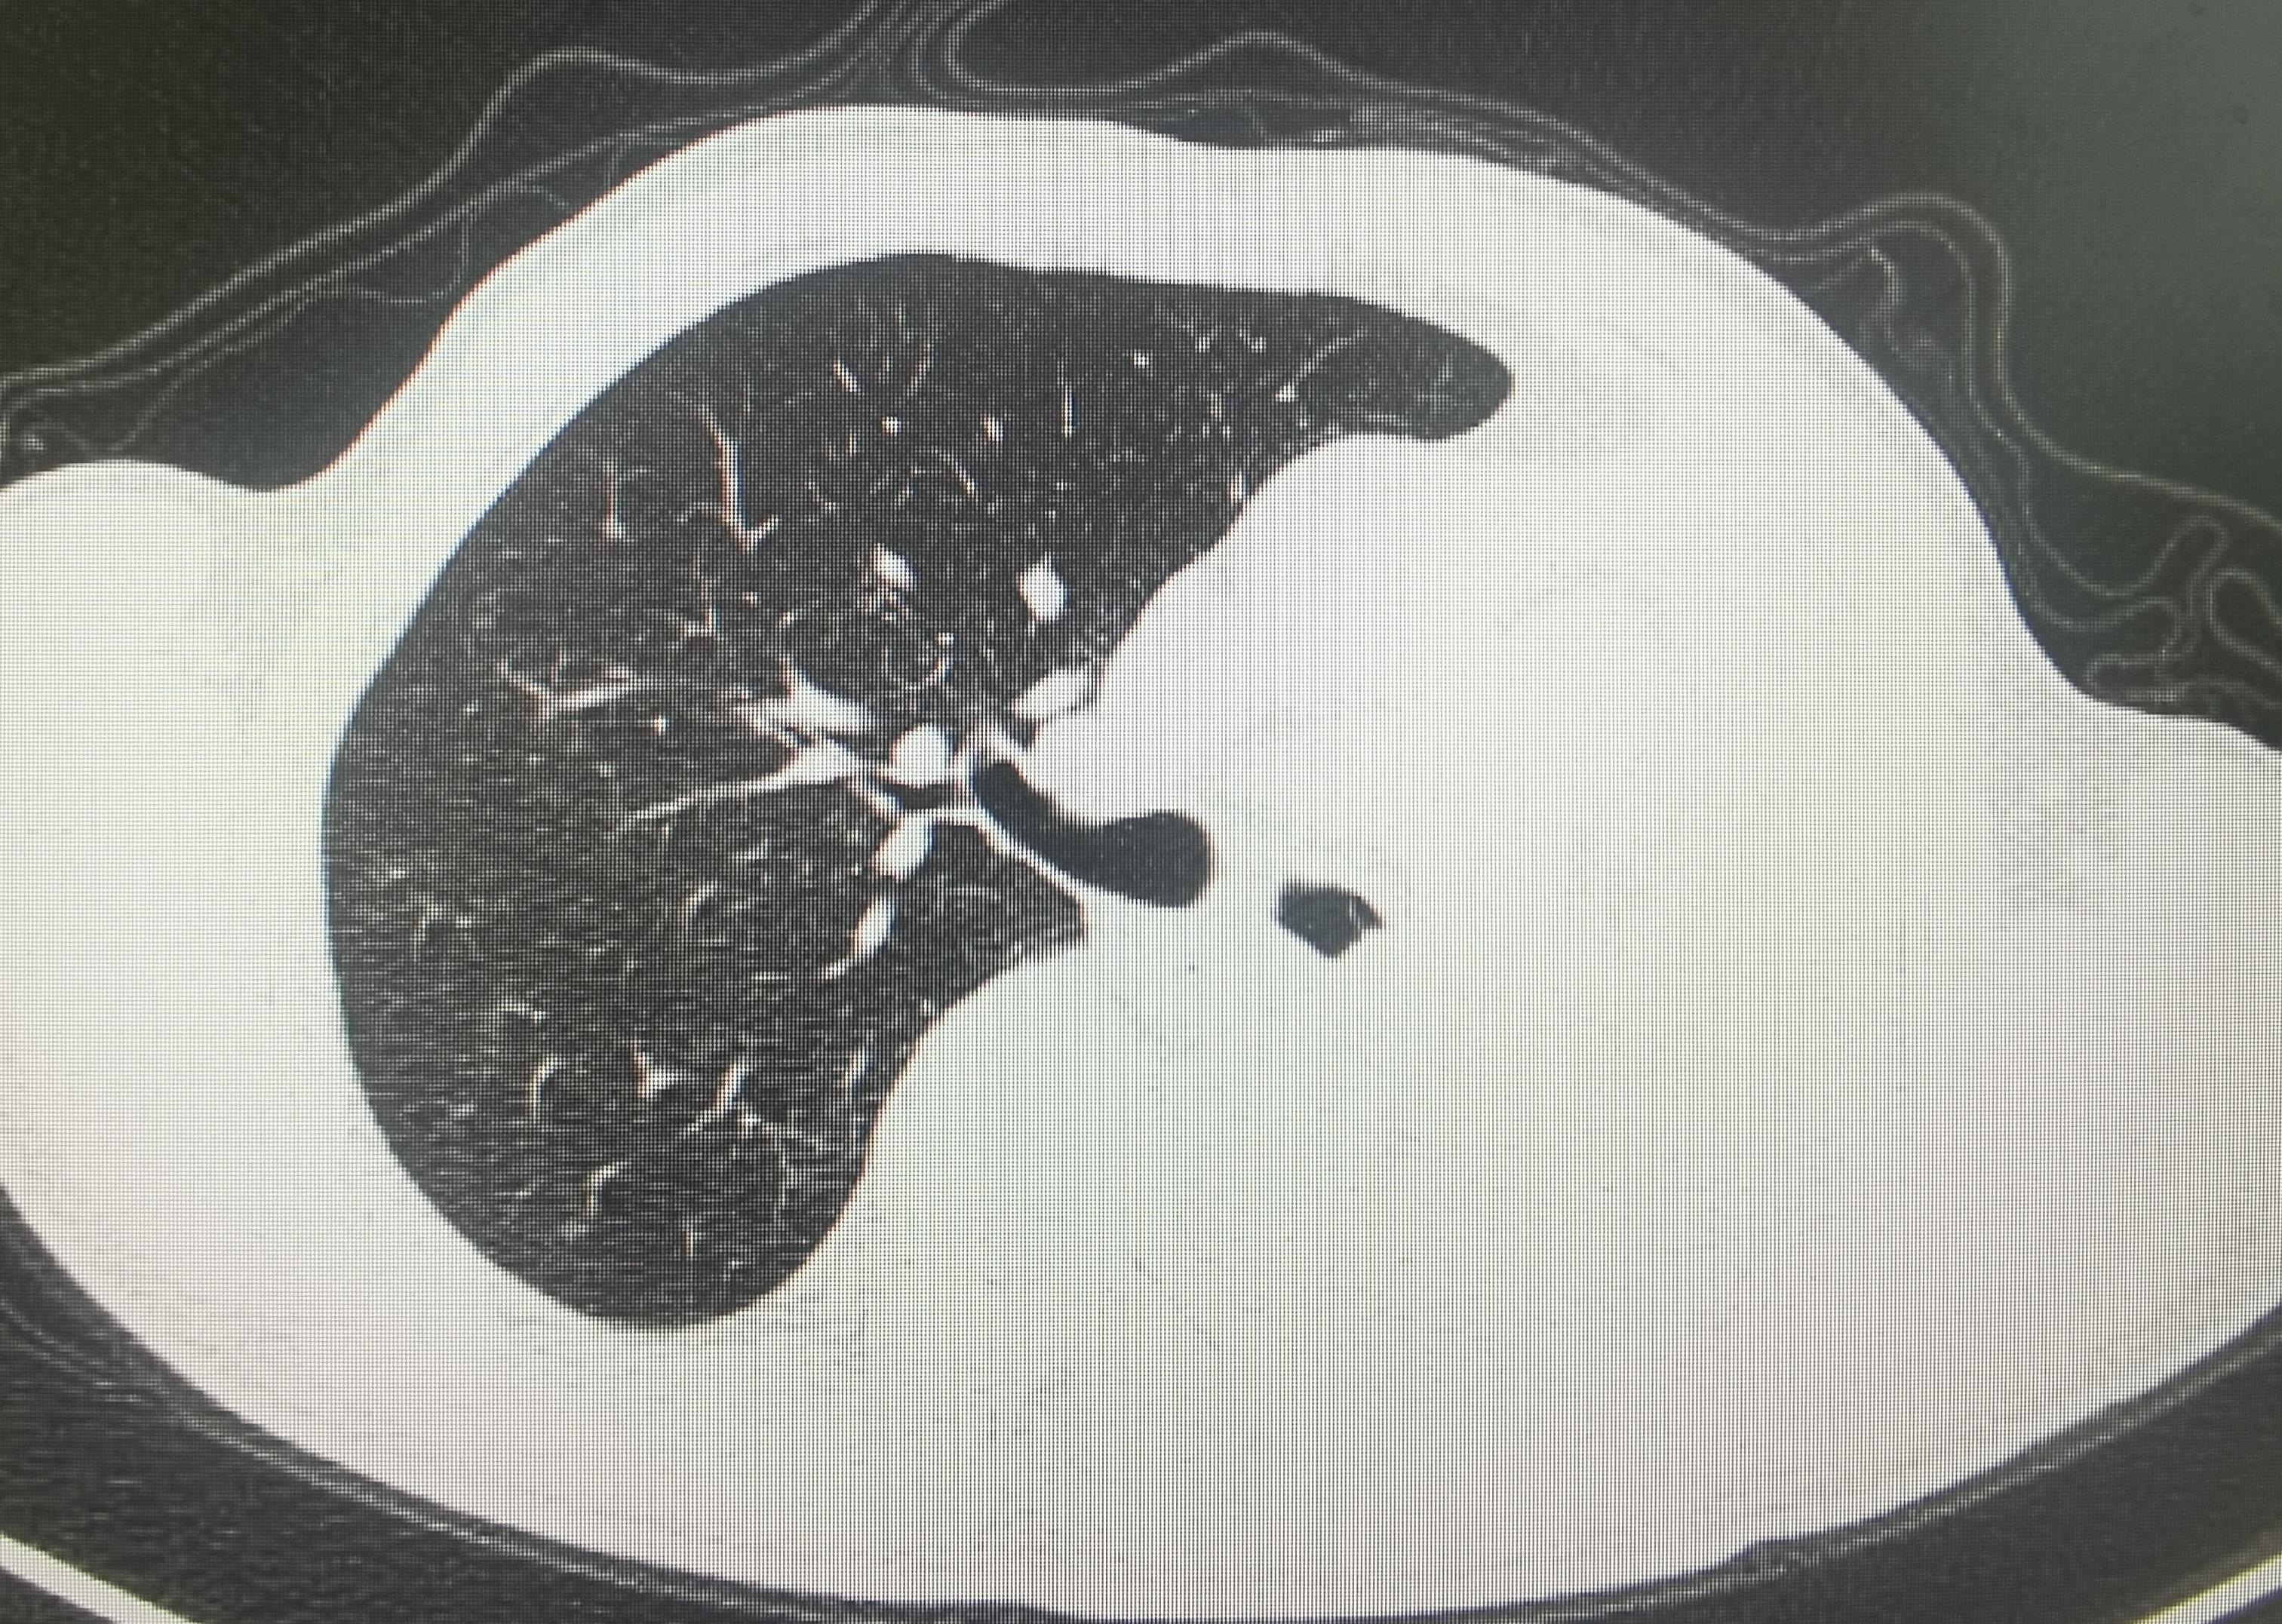

肺癌患者,左肺完全肺不张。经过一次bace的治疗,一个月后复查CT左肺完全复张,为后续全身治疗提供条件